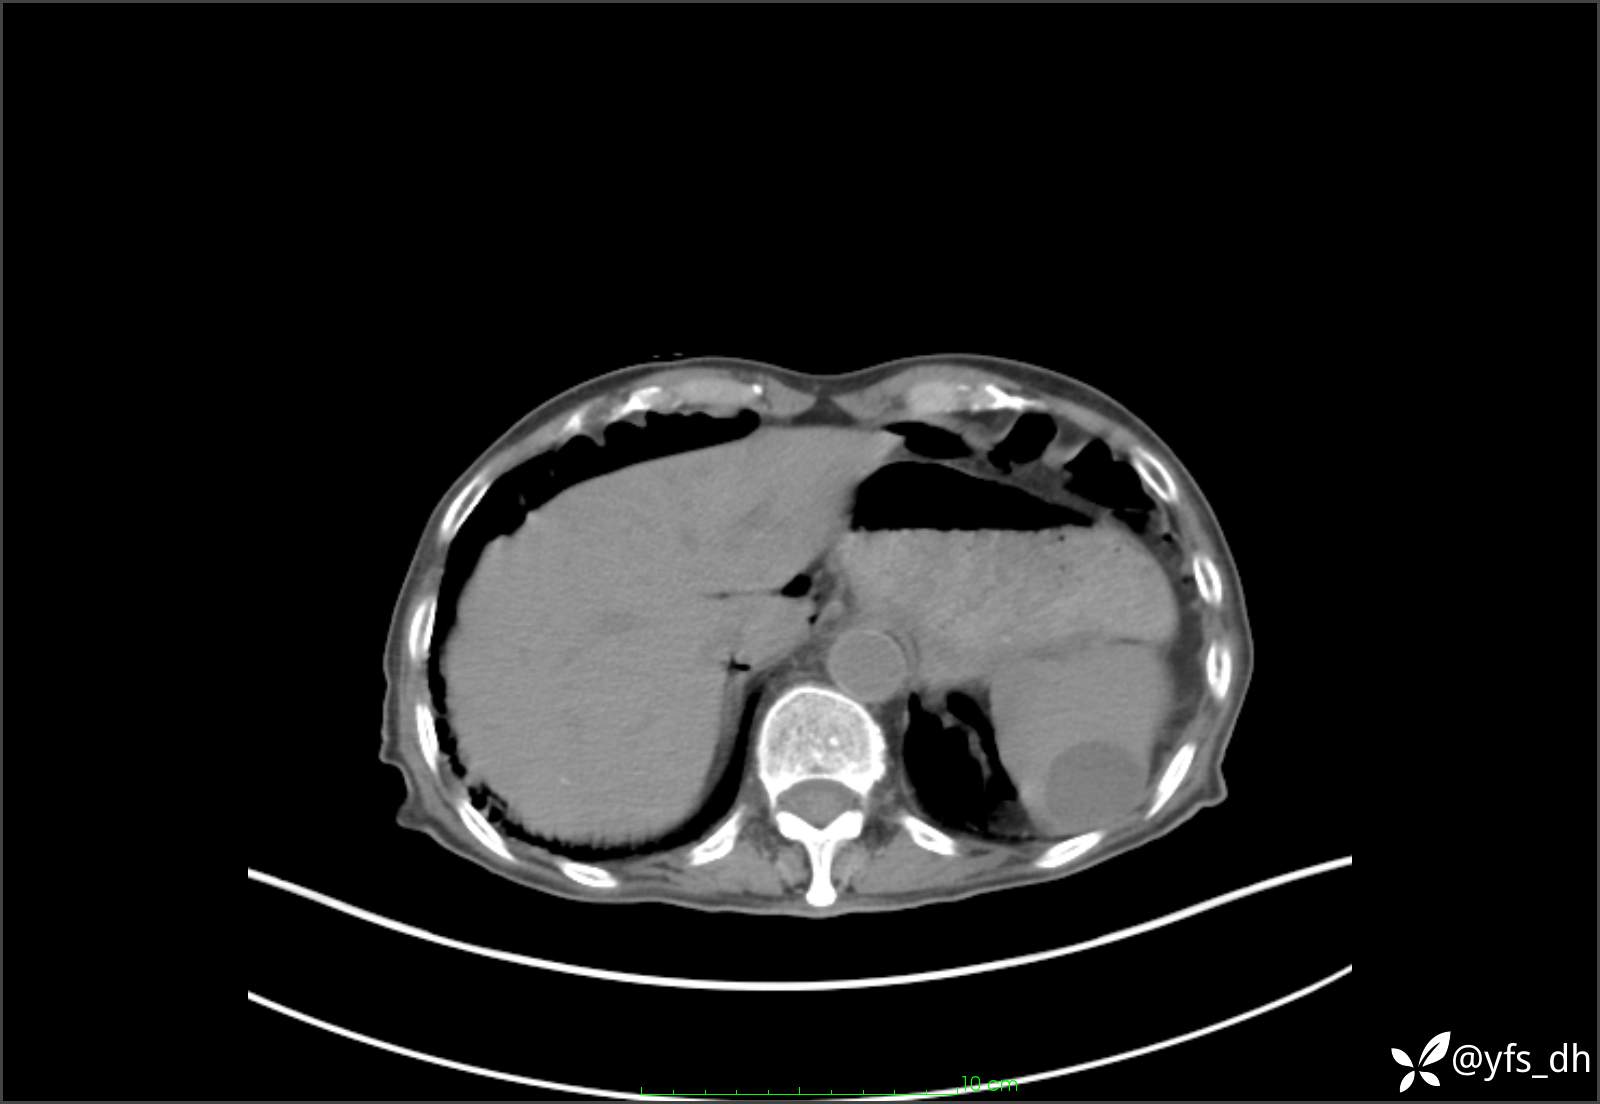

1.简要病史:患者4天前突发上腹部疼痛不适,但可以忍受。3小时前饭后突然加重,不能忍受后就诊。

2.简要手术记录:术中见腹盆腔大量肠液及粪便,乙状结肠中下段见一约3cm的破口。